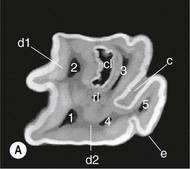

image image image

Fig. 13.43 Radiograph (A) and CT images (B and C) of a compound odontoma in a 2-year-old TB colt.

(Images courtesy of J. Easley.)